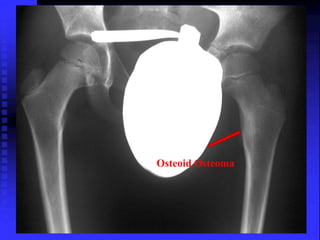

Osteoid Osteoma